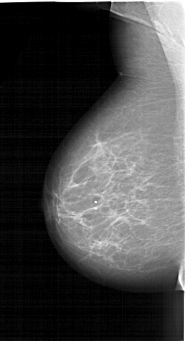

A_1264_1.LEFT_MLO

LEFT_MLO LINES 6466 PIXELS_PER_LINE 3511 BITS_PER_PIXEL 12 RESOLUTION 43.5 NON_OVERLAY